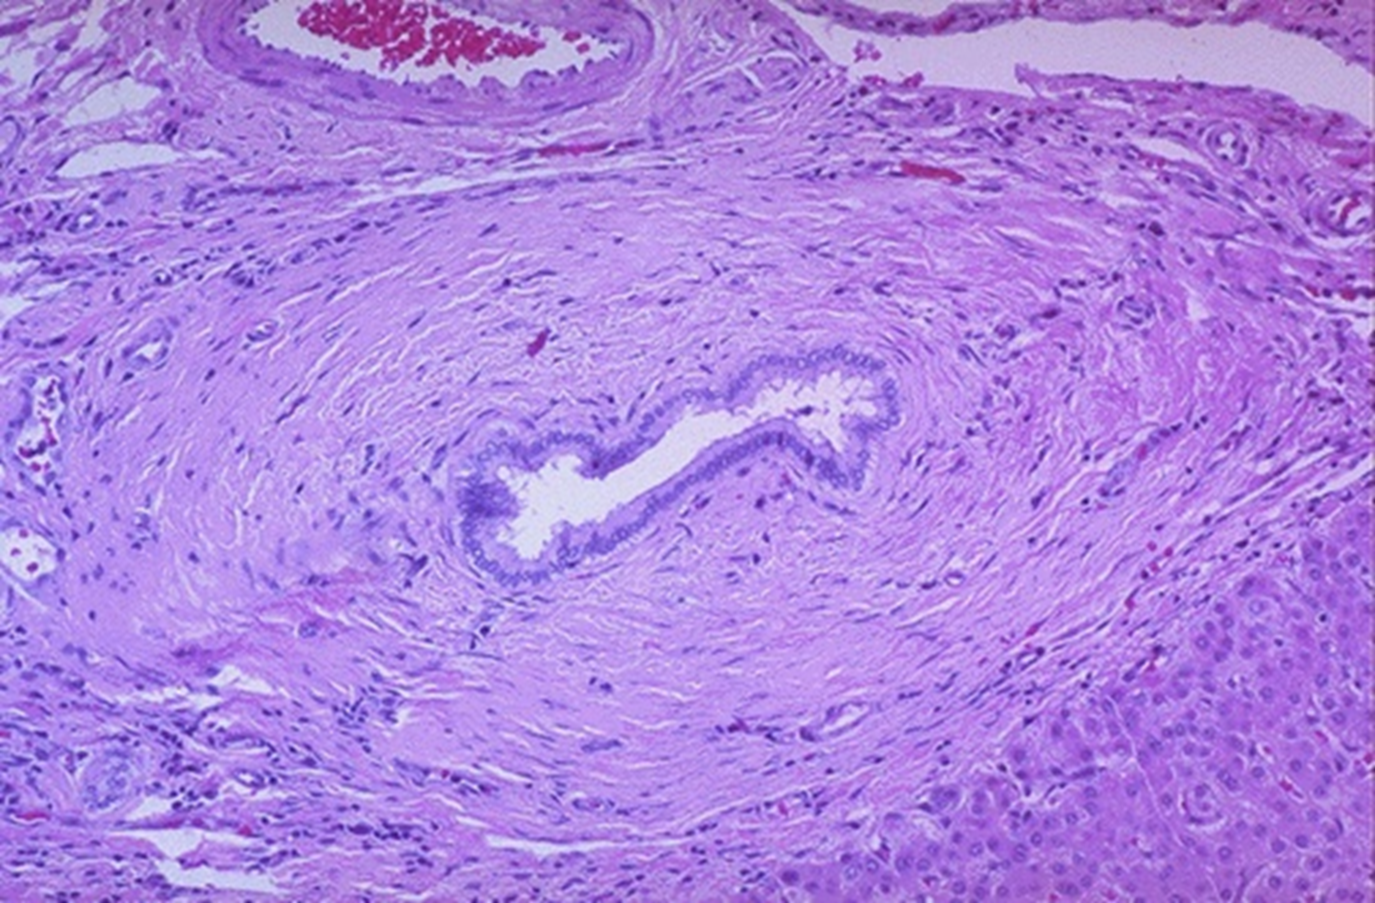

immune mediated destruction of small intrahepatic bile ducts

PBC

PBC florid duct lesion